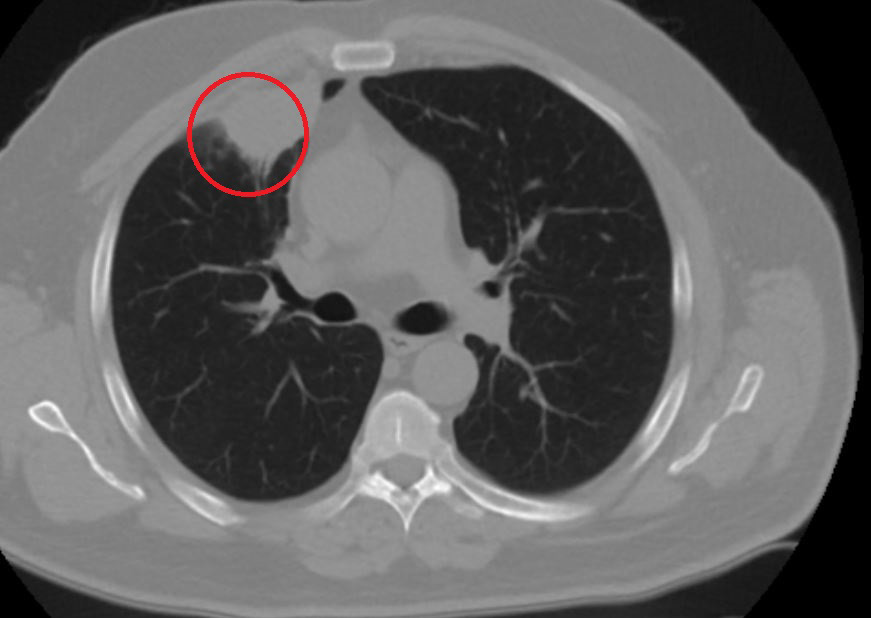

"Hasta bize başvurdu ve göğüs ağrısı şikayeti vardı. Öksürük, nefes darlığı, balgam çıkarma, ateş gibi şikayetleri yoktu. Hastayı biz de değerlendirdik ve ameliyat olmasına karar verdik. Çünkü akciğer kanserine çok benzer radyolojik bulguları vardı. Sağlık Bakanlığımızın kuralları gereği her hastayı ameliyat öncesi PCR testi yapılır. Biz de ameliyat gecesi hastadan PCR testi aldık ve testi pozitif geldi. Ameliyatımızı 14 gün erteledik ve hastamıza koronavirüs tedavisi uygulandı. Hasta 14'üncü gün tekrar bize başvurdu ve yapılan PCR testi negatif çıktı. Yeni bir tomografi çektik ve tümörün tamamen ortadan kalktığını gördük. Şimdi sonuç bilgilerinden başlangıca gittiğimizde, bu bir akciğer kanseri olsaydı, ortadan kalkması mümkün değildi. Başka bir patolojiye bağlı durum olsaydı, yine verdiğimiz tedaviyle ortadan kalkmasını çok beklemeyiz. Antiviral tedavisi verdik ve hastanın radyolojik bulguları neredeyse tamamen normale döndü. Hastaya bunu izah ettik, 'Dünya literatüründe hiç görülmeyen bir radyolojik bulgu' diyerek. Bu gördüğümüz manzara artık hastanın akciğer grafisinde yok, akciğer kanseri değil. "

Hastayı takip etmeye devam ettiklerini belirten Kozanlı, 2 yıldır dünyayı etkisi altına alan koronavirüsün akciğer kanserini taklit ettiğini, böyle bir durumla ilk defa karşılaştıklarını söyledi.

Hem Türkiye'de hem de diğer ülkelerde buna benzer bir vakanın olup olmadığını araştırdığını ifade eden Kozanlı, "Bizim hastamızda akciğer tümörünü taklit eden bir kitle vardı. Ve biz bunu dünya literatüründe hiç görmemiştik. Bununla ilgili geniş çaplı bir araştırma yaptım. Hem kendi deneyimlerimden hem kendi hastanemizde yatan hastalardan yola çıkarak birçok hastanın radyolojik bulgularına baktık. Dünya literatürlerini karıştırdım, diğer arkadaşlarıma danıştım, benzeri bulguya rastlamadım" diye konuştu.